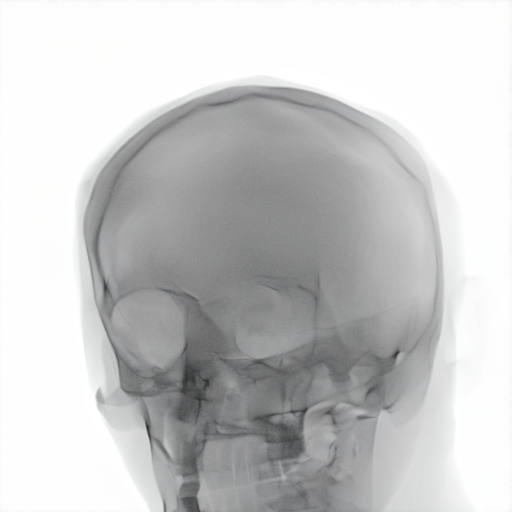

Refer to caption

Figure 2: Dataset overview. The synthetic domain contains Low and High dosage samples generated using the Mentice VIST® simulator; the real domain includes Low, Normal, and Exposure dosage categories acquired from a skull phantom using the Philips Azurion IGT system.

We develop and release a new dataset of real and synthetic head X-ray images, X-DigiSkull, to study the domain adaptation. The dataset consists of synthetic X-ray images of a human skull generated using the Mentice VIST® simulator 111https://www.mentice.com/simulator/vist-g7. Real‑time X‑rays are generated by holding the 3D voxel “patient” head model with per‑voxel attenuation, casting one ray per detector pixel to form a digitally reconstructed radiograph and then approximating scatter, focal‑spot and detector blur, grid/heel effects and detector response, adding quantum/read noise and final image post-processing as the C‑arm and devices move. Real images are acquired from a clinical-grade physical skull phantom using the Philips Azurion Image Guided Therapy (IGT) system. Images are captured from common IGT working positions for neuro procedures. The dataset consists of multiple orientations and is available in three different radiation dose settings: low, normal, and exposure (Philips exclusive), the latter offering enhanced image quality and detail, as shown in Figure 2. This consists of viewing angles rz[40,+40]r_{z}\in[-40^{\circ},+40^{\circ}], ry[40,+40]r_{y}\in[-40^{\circ},+40^{\circ}], rx[40,+40]r_{x}\in[-40^{\circ},+40^{\circ}] with respect to the starting position in 10 increments and up to 3 images at each position to capture the noise present. This results in a total of 2,187 real images. The coordinate systems of the real and synthetic environment are aligned and synthetic images are rendered to approximate the same viewpoints as the real phantom images with the patient table starting at a similar position.The head 3D model used in the simulation is meticulously built from a real clinical case. We capture the synthetic images in finer increments of 5 across the three angles, producing the 5,832 (18318^{3}) images 222Data available at https://zenodo.org/records/16535437. The aim of this alignment is not to achieve precise supervised image translation, but rather to establish a consistent reference structure that preserves spatial features. The composition of the dataset is summarized in Table 1, which contains information on the splits and the number of images available. All images are cropped and resized to 780×\times780 pixels. The test set is obtained by uniformly sampling 15% of viewing angles and corresponding images to ensure a representative distribution. For our experiments, we focus on the task of converting synthetic images at high dose to real images at normal dose.